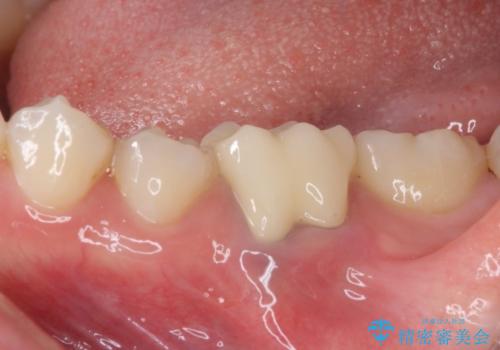

- 前歯のデコボコが気になるとのことで来院された患者様です。

目立たない装置と金属のワイヤーで矯正治療を行うこととしました。

奥の銀歯も気になっていたため、矯正治療後にセラミッククラウンにて補綴することとしました。

1年半程度の期間を見込んでいましたが、上下の真ん中の位置をできる限り合わせるための調整に少し時間がかかってしまいました。

咬み合わせが安定し、前歯の汚れも付きにくくなりました。